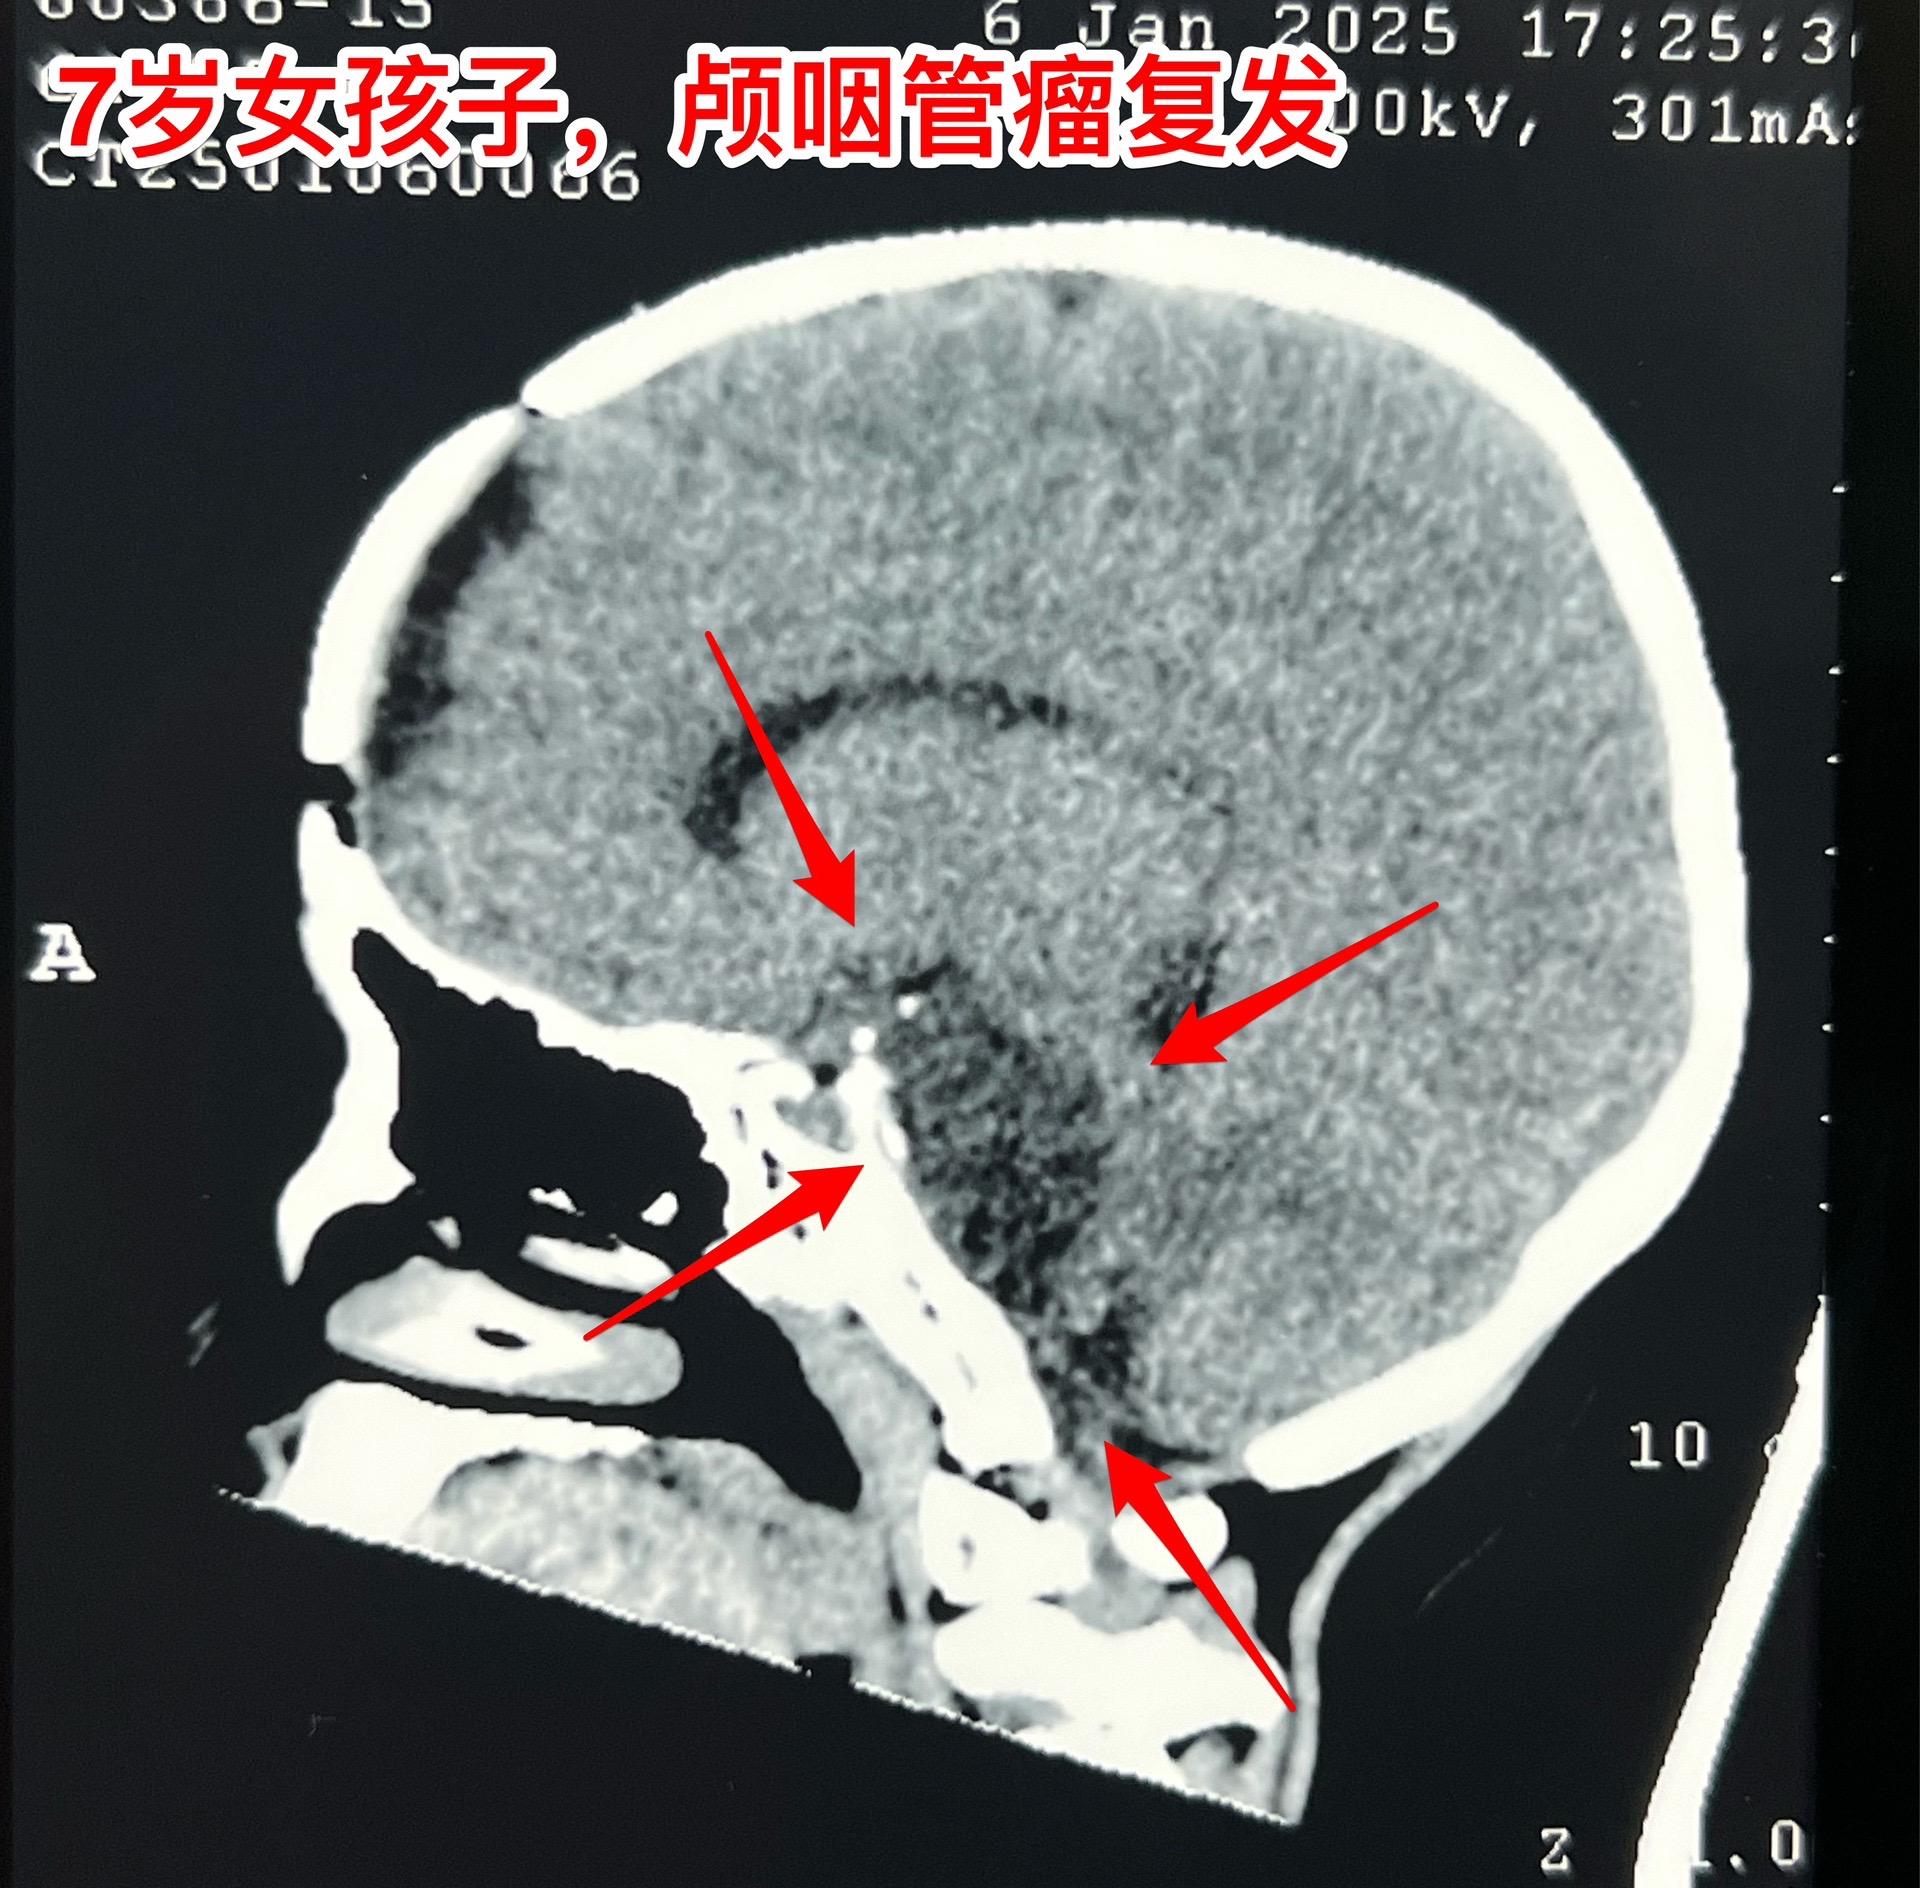

颅咽管瘤复发,看起来是一个瘤其实有三个。7岁女孩子,颅咽管瘤复发。从C...